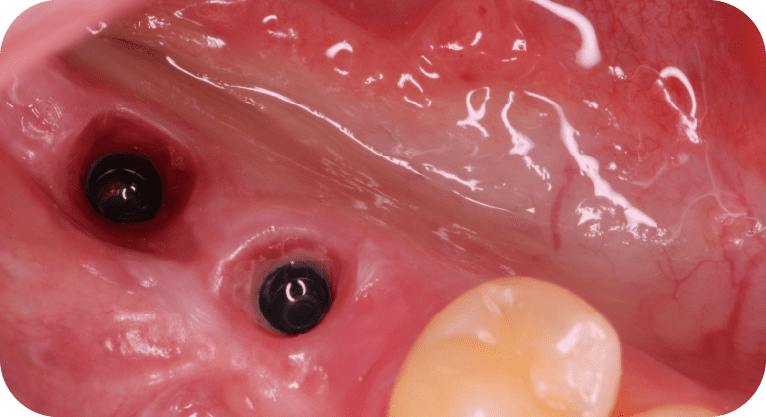

Paciente femenino, “42” años

Tratamiento: Implante dental

El paciente acudió a la clínica tras haber perdido dos molares por caries avanzada, lo que afectaba su función masticatoria. Para restaurar la zona edéntula, se realizó la colocación de implantes dentales en los espacios correspondientes, devolviendo así la capacidad de masticación, previniendo la pérdida ósea y manteniendo la alineación de las piezas adyacentes, con resultados funcionales y estéticos satisfactorios.